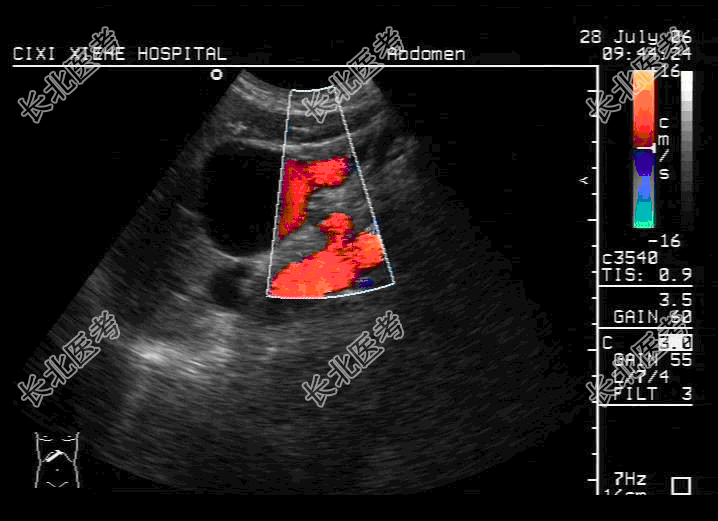

- 单项选择题女,82岁, 右乳癌根治术后5个月来我院化疗。入院后各项化验结果均正常范围,行超声检查时发现第一肝门部见50mm×43mm囊性包块, 边界清,其内透声可, 余肝内未见明显异常回声,未见肝内、外胆管扩张。胆囊、胰腺未见明显异常。超声声像图如图, 那么应诊断为

A、小网膜囊肿

B、先天性胆总管囊状扩张

C、门静脉瘤

D、肝囊肿

E、以上都不是